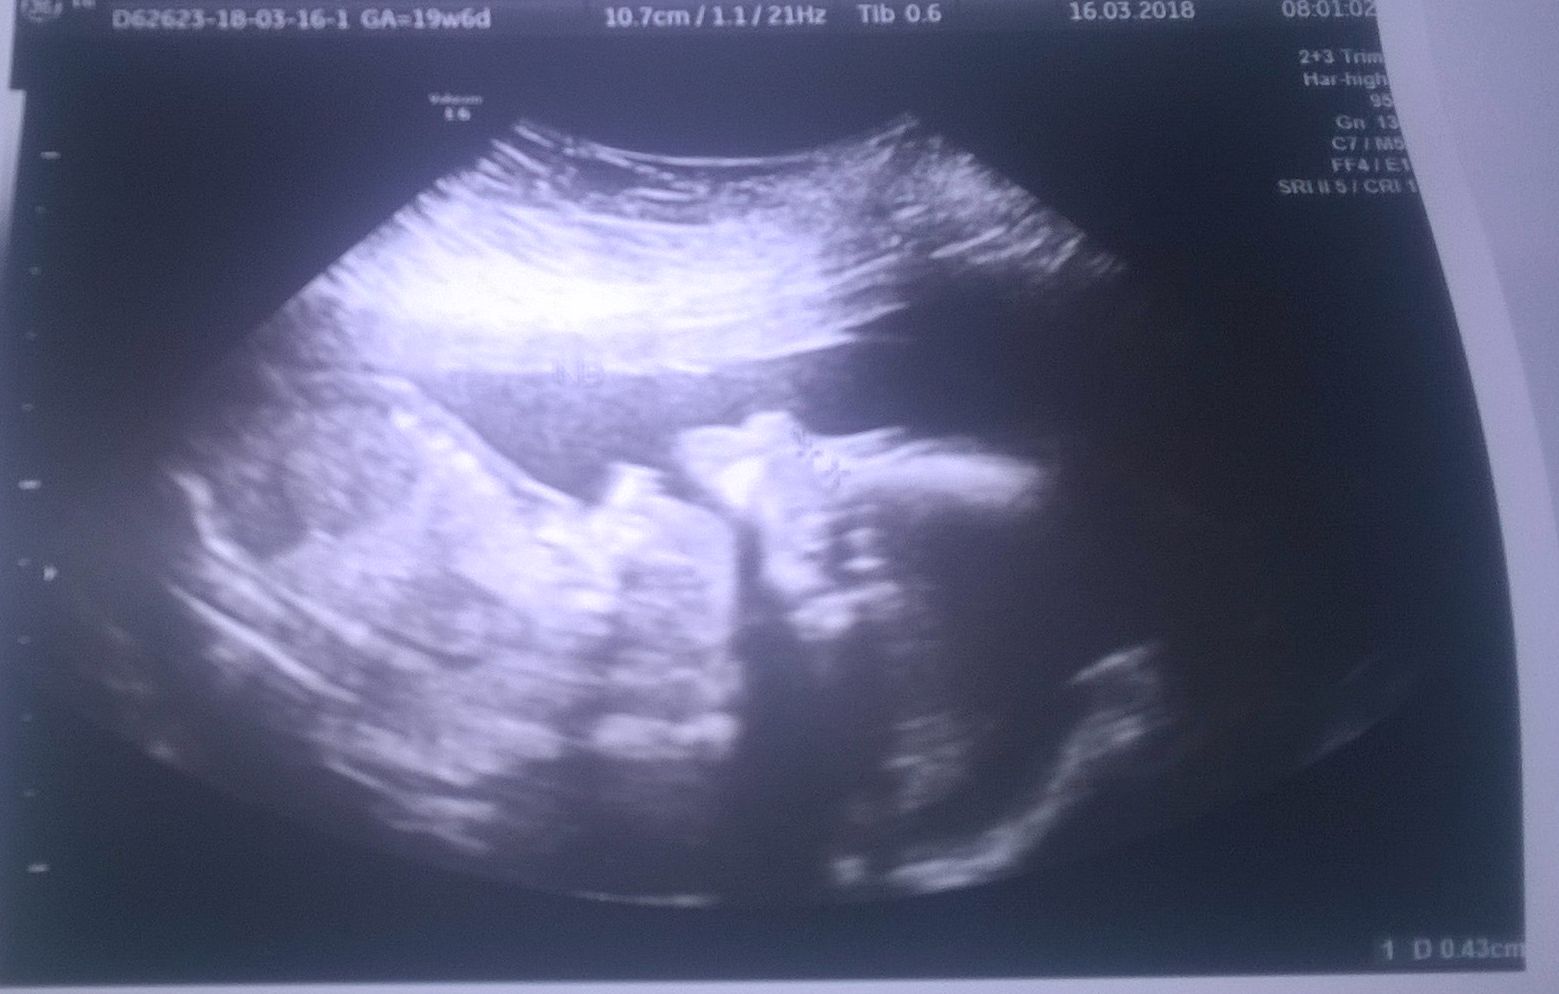

Będę miała dwie córki

Ułożone są, jak to ona określiła? Podłużnie miednicowo, czyli są dupkami do dołu, zwrócone do siebie twarzyczkami

Jedną udało się uchwycić w 3D, ale nie drukowaliśmy. Ważą praktycznie tyle samo: 354g i 359g ile mają cm nie wiem, bo dzisiaj tego nie mierzyła. No i termin z USG zmienił się z 31 lipca na 3 sierpnia

Dodam, że lekarka mi powiedziała, że dziewczyny są tak podobne wagowo, że jakby się sklonowały. Fajnie w ogóle wyglądała przegroda owodniowa, jakby falowała jakaś nitka. A i foteczki mam buziolków

i muszelek. Jedna akurat otwarła dziubek, to wygląda dziwnie.

Zobacz załącznik 842712 Zobacz załącznik 842713 Zobacz załącznik 842714 Zobacz załącznik 842715